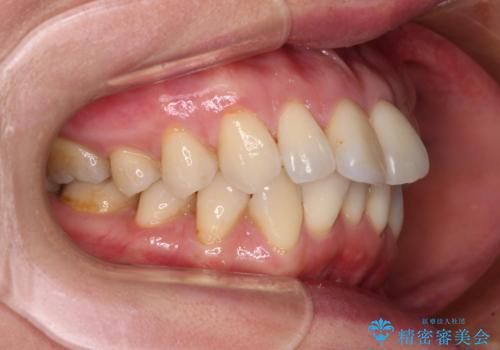

前方に飛び出した前歯 ワイヤー装置での抜歯矯正

- 前方に飛び出した前歯を気にして来院された患者様です。

通常であれば上下左右の第一小臼歯4本を抜歯して口元の突出感を改善しますが、下顎前歯が1本欠損しており、上下の歯の数がアンバランスであるため、4本抜歯するかどうか悩むところでした。

上顎前歯はやや小さめで、下顎前歯はやや大きめであったため、上下左右4本を抜歯しても左右奥歯の咬み合わせは理想に近い状態を達成できると判断し、上下左右の第一小臼歯4本を抜歯し、ワイヤー装置にて矯正治療を行うこととしました。